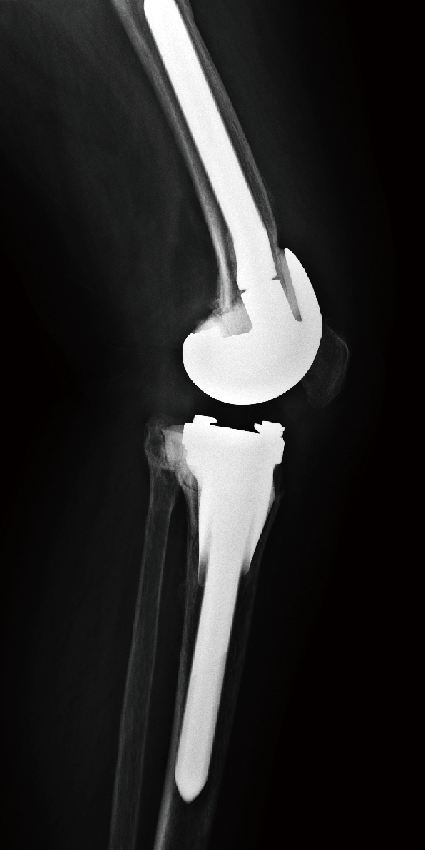

单髁翻修

单髁膝关节置换术后8年,塌陷,接受全膝关节表面置换术